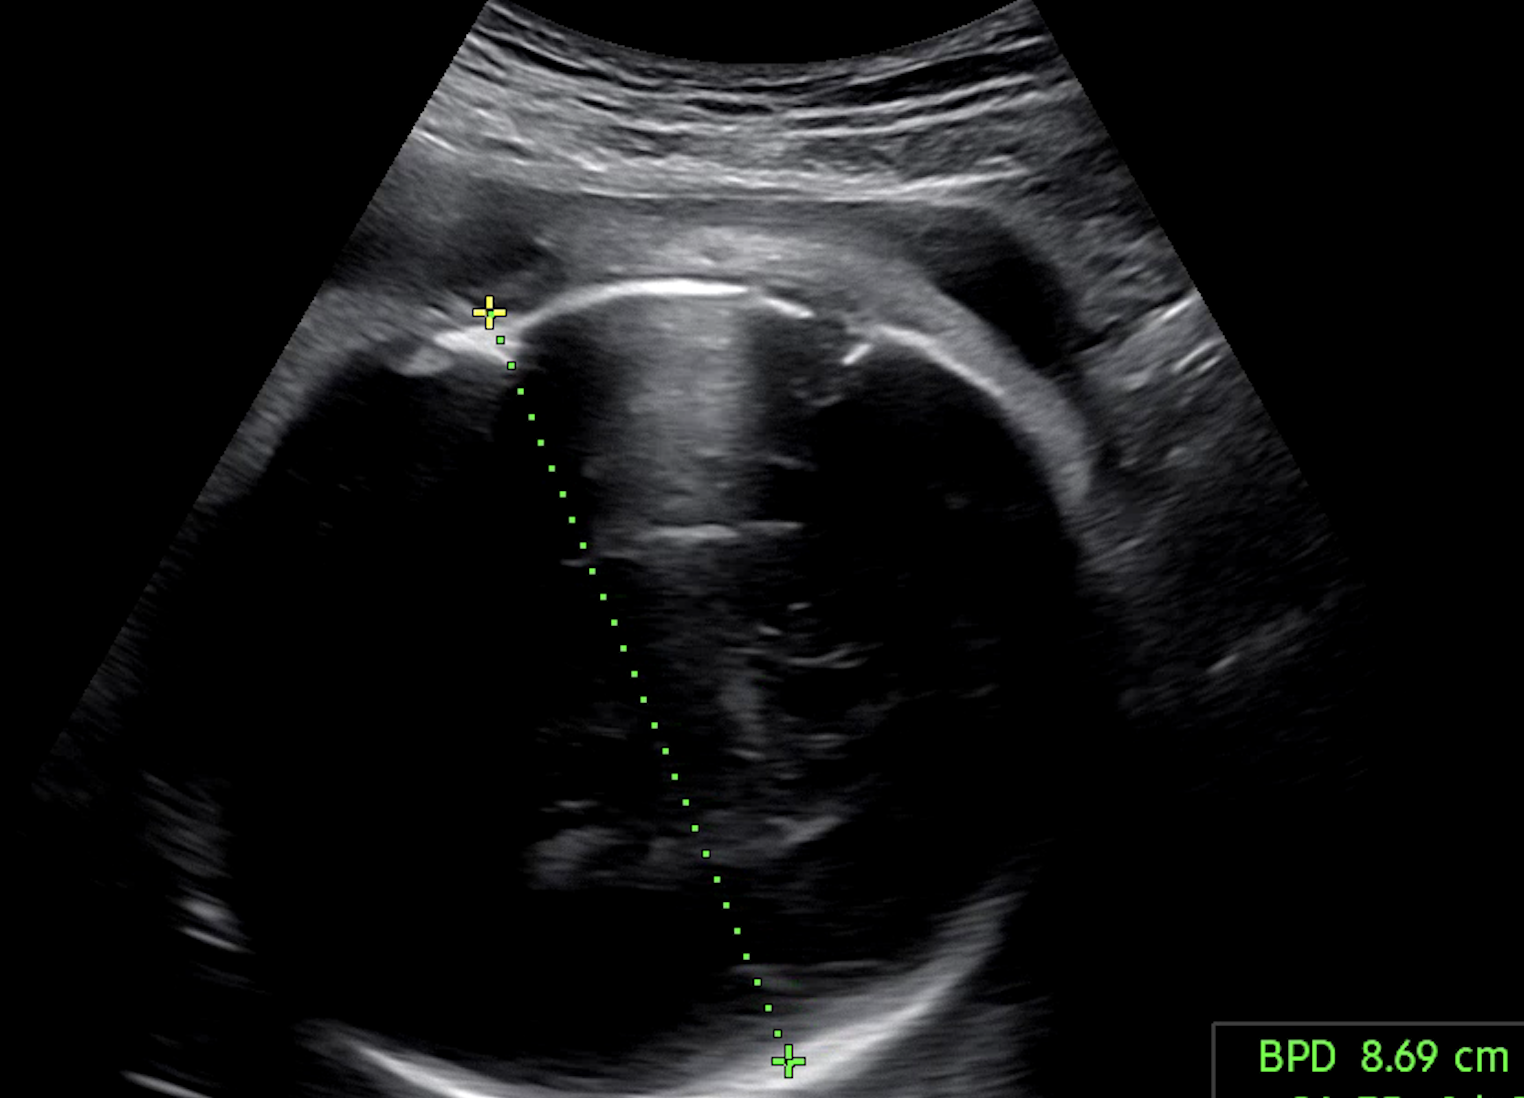

다른 메트릭에 비해서 입체 초음파 이미지의 경우, 굉장히 잘 분류되었다. 그리고 그 이유가 궁금했다. chatGPT 나 구글링 통해서 여러 차례... 아니 며칠을 물었다. 입체 초음파의 학습 샘플들이 모델 입장에서 "쉬운 정답들 (Easy Positives/Negatives)" 이지 않았을까.. 싶다. 그리고 로직을 다시 복기해보니 편차가 있는 클래스들 (어려운 부정 샘플 (Hard Negatives)) 은 별도 가중치 없이 학습되고 있다는 것도 깨달았다. 그래서 찾아보다가 Hard Negtive Learning 알게 되었다. 뭐든 해봐야 알 수 있으니 바로 도입해봤다. 학습 순서는 다음과 같다.

입체 초음파 분류 자체는 신뢰도가 높은 편이다. 초기 프로토타입에 불과했던 이미지 분류 기능이, 이제는 실서비스에 녹일 수 있을 만큼 안정성과 완성도를 갖췄다. 하지만 나의 최종적인 목표는 다양한 생체 메트릭을 활용/분석해서 의미있는 예측 모델을 만들고 싶다. 그래서 오늘도 삽질 중이다.🔥